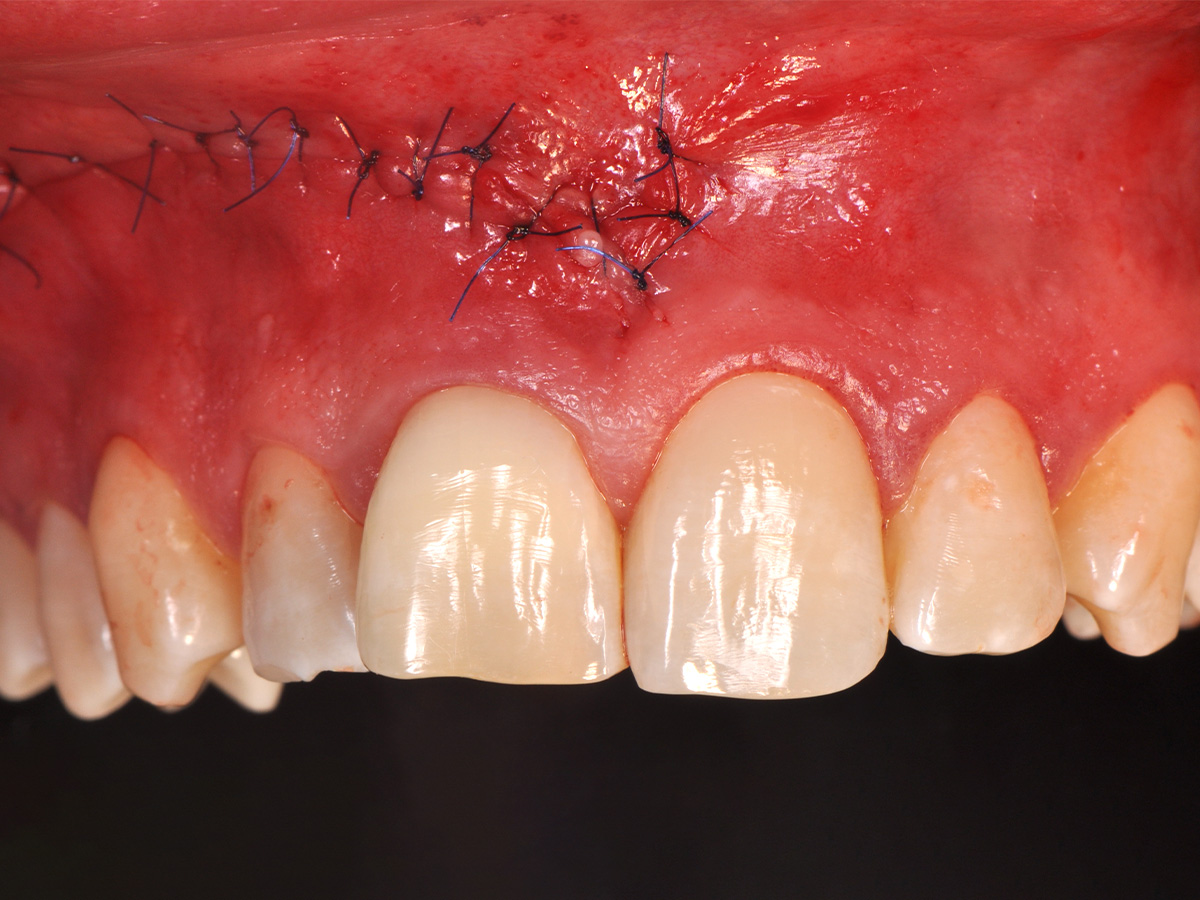

Abbildung 15

Der Wundverschluss erfolgte einschichtig mit nicht resorbierbarem Nahtmaterial (Seralene® 5-0 DS-15).

Mit der Patientin wurde der Versuch des Zahnerhaltes trotz ausgedehnter Zyste besprochen. Gleichzeitig sollte das Zystenlumen zu einer sicheren ossären Durchbauung geführt werden, um eine implantologische Sofortversorgung vorzubereiten, falls zu einem späteren Zeitpunkt eine Zahnentfernung notwendig werden sollte. In der Phase vor der geplanten Operation wurden die Wurzelkanalfüllungen an Zahn 11 und 12 durch einen Endodontologen alio loco revidiert. Die Schnittführung wurde aufgrund des bestehenden „Gummy Smile“ hoch im Vestibulum geführt – so konnte die delikate Parodontalstruktur in ihrer Form unangetastet belassen werden, um einen möglichst optimalen ästhetischen Erfolg zu erreichen (Abb. 8, 9). Nach vestibulärer Freilegung wurde die Zyste vollständig entfernt und zur histopathologischen Untersuchung eingesandt (Abb. 10). Anschließend erfolgte eine Wurzelspitzenresektion an den Zähnen 11 und 12 durch die vestibuläre ossäre Perforation (Abb. 11), gefolgt von einer ultraschallbasierten, retrograden Kanalaufbereitung und Abdichtung mit MTA. Um die knöcherne Durchbauung am Boden der Zyste osteoinduktiv zu unterstützen, wurden mit Hilfe eines mechanischen Knochenschabers aus dem Bereich des rechten naso-palatinalen Pfeilers Knochenchips entnommen und als erste basale Augmentationsschicht in den ossären Defekt eingebracht (Abb. 12). Der größere Anteil von 80 % des Defektvolumens wurde mit einem vollständig resorbierbaren, xenogenen Augmentationsmaterial aufgefüllt (Abb. 13) (mp3®, OsteoBiol®). Der Defekt wurde zum Vestibulum hin mit einer stabilen, vollständig degradierbaren Membran abgedeckt (Abb. 14) (Soft Cortical Lamina, OsteoBiol®). Zum einen wurde hiermit im Sinne der GBR das Weichgewebe vom Augmentat getrennt. Zum anderen verhinderte die stabile Membran das Einwachsen eines Weichgewebeankers in den Defekt und damit eine narbige Verziehung im Vestibulum. Um eine Verschiebung der Membran zu vermeiden, wurde diese mit zwei Titanpins in der Kortikalis fixiert. Die Pins wurden bei Beschwerdefreiheit in situ belassen (Titan-Bone-Pin-System). Der Wundverschluss erfolgte einschichtig mit nicht resorbierbarem Nahtmaterial (Abb. 15) (Seralene® 5-0 DS-15). Peri- und postoperativ wurde eine antibiotische Abschirmung unter Fortführung für insgesamt drei Tage mit Amoxiclav 875/125 1-0-1 durchgeführt.